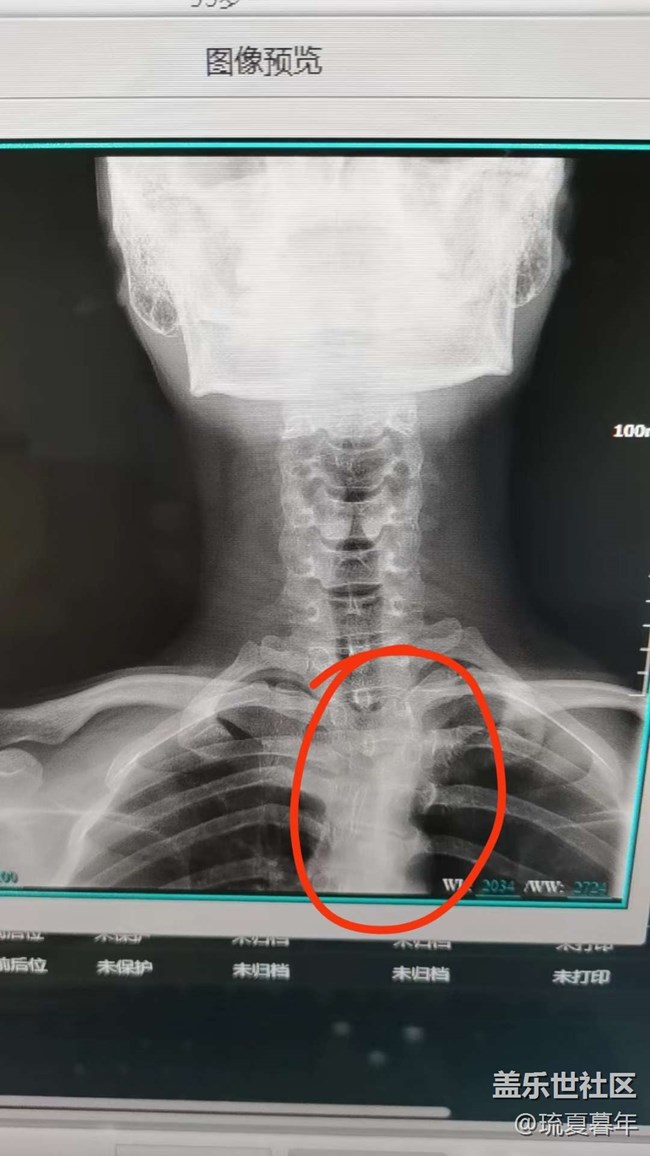

有一点点脊柱侧弯 图片

但是问题不大,属于生理性的,大家平时注意